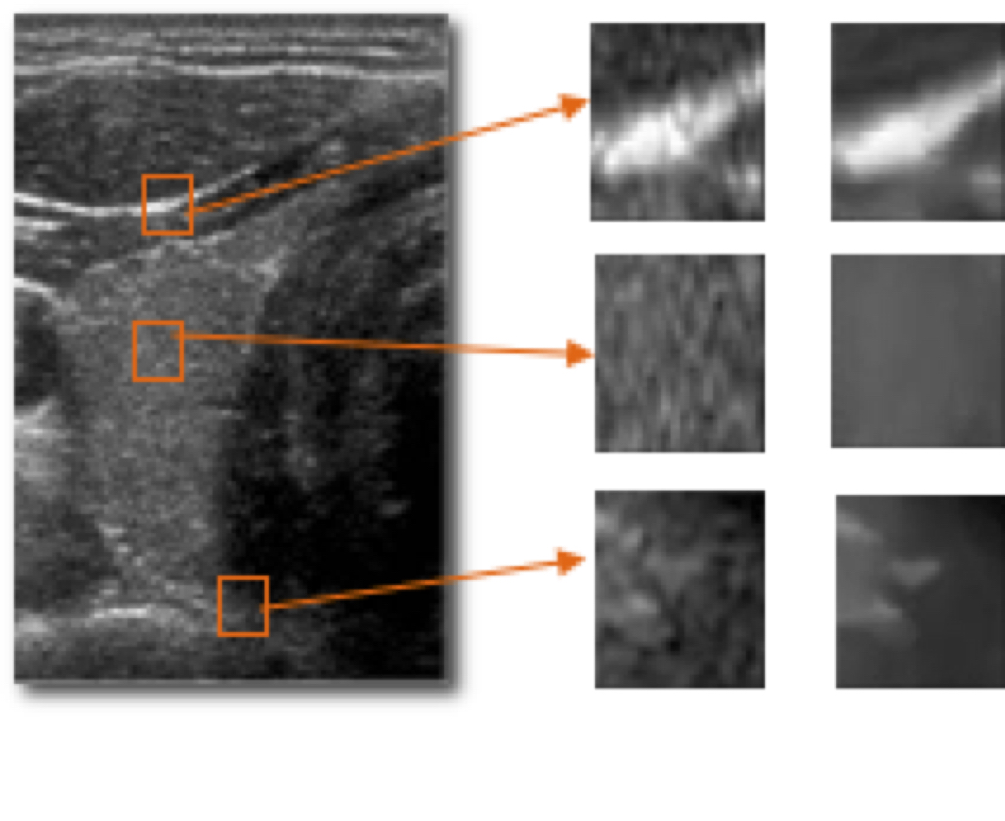

-SRI – Speckle Reduction Imaging

Software de reducción del punteado en la imagen ecográfica. Un conjunto de algoritmos aplicados a la imagen nos permiten elegir hasta 5 niveles de reducción del ruido. Su uso permite aumentar la definición en la imagen y supone la eliminación de ruido y artefactos.

-CROSSXBEAM

La tecnología compuesta espacial, exclusiva de GE, es una técnica de adquisición para mejorar los márgenes anatómicos, lo que a su vez mejora el aspecto de las estructuras fisiológicas. Un nuevo algoritmo compuesto digital amplía las ventajas de CrossXBeam™ a los exámenes en Doppler Color y cuenta con un campo de visión ampliado que permite obtener una claridad de imagen y una resolución de contraste sin precedentes en cualquier modalidad de trabajo.